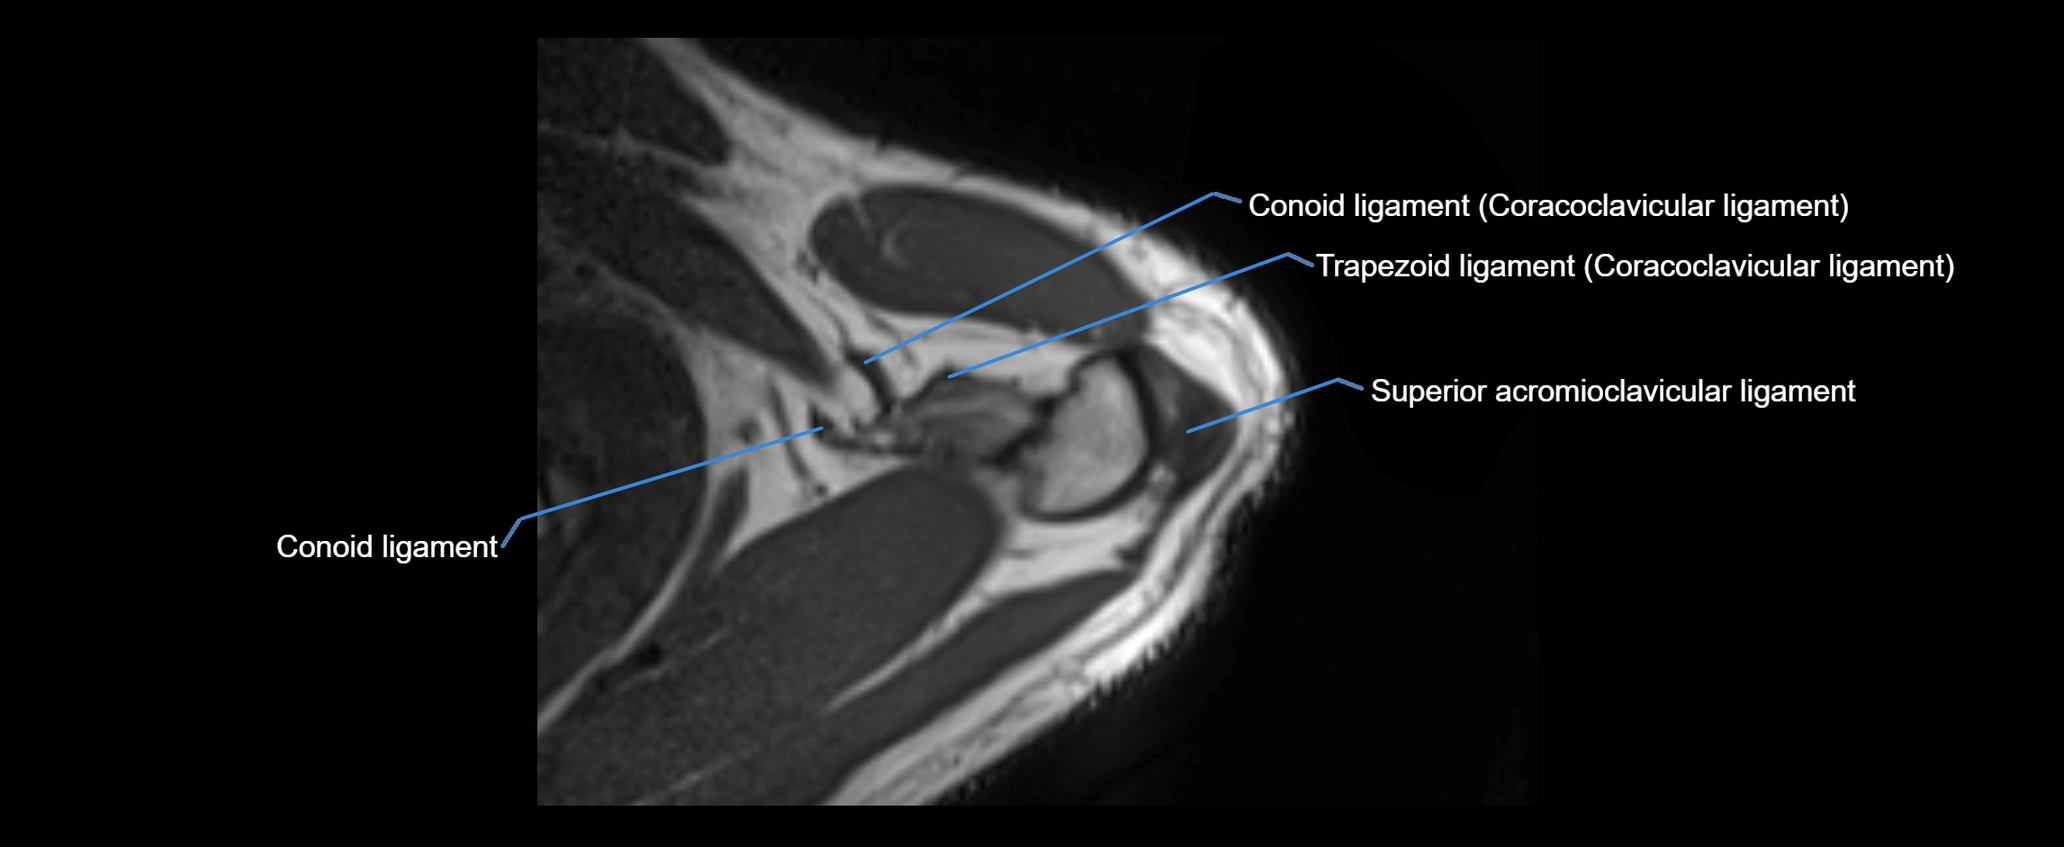

CT image

image

CT Appearance

Non-Contrast CT:

• Ligament: Not directly visualized due to small size and low density.

• Bony landmarks: Lateral clavicle and acromion clearly seen; cortical margins well defined.

• Pathology: Detects fractures, joint subluxation, osteophytes, and degenerative changes.

• Alignment assessment: Evaluates AC joint spacing and clavicular displacement.

Post-Contrast CT (standard):

• Ligament itself: Non-enhancing fibrous band.

• Inflamed capsule or soft tissue: May show enhancement.

• Useful for: Evaluating post-traumatic deformities, ossified ligaments, and chronic AC joint arthropathy.